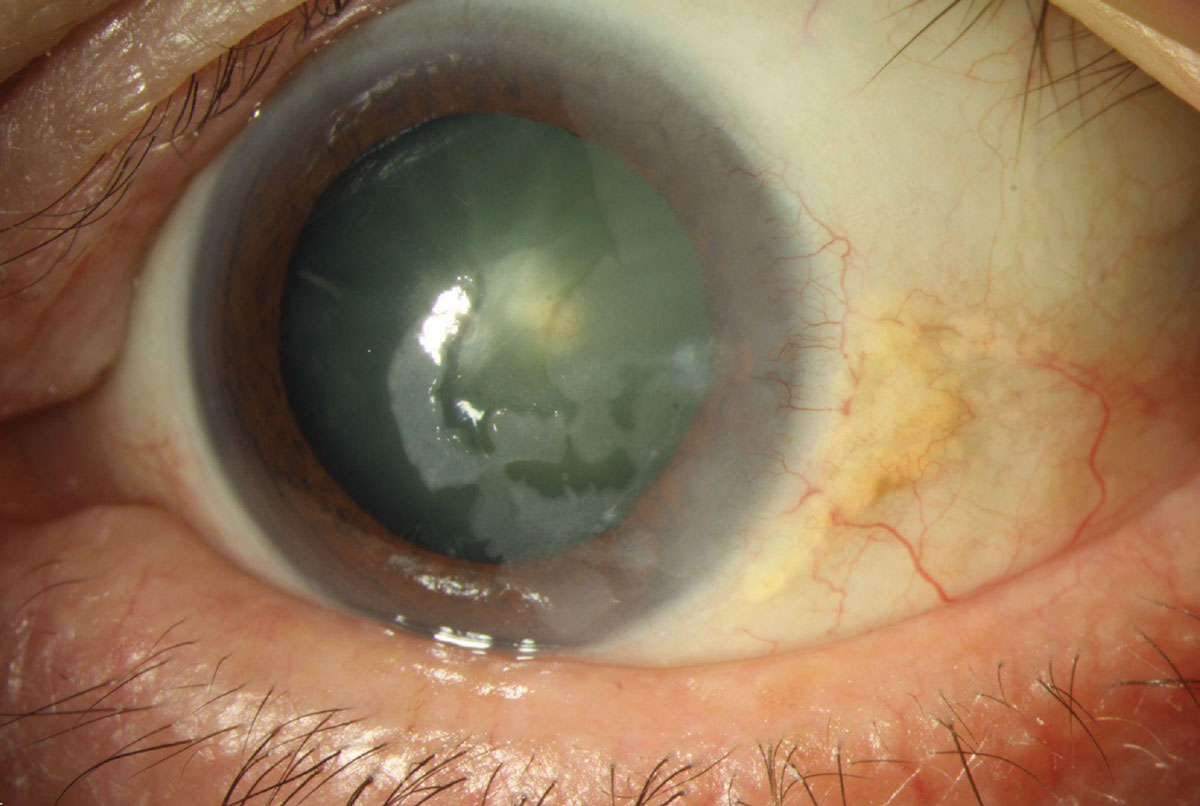

각막상피 이상성숙증(epithelial dysmaturation)은

주로 각막 상피만 침범하는 질환으로 광범위하게

얼어있는듯한 모양의 각막상피 혼탁이 발생하게됩니다.

각막상피의 투명도가 없어지면서 유백색의 병변으로 상피의 혼탁이 관찰되며,

주로 각막 상피만을 침범합니다.

이는 양성의 병변으로 서서히 진행하거나, 그대로 유지되며,

조직학적으로 핵크기만 다른, 정상과 비슷한 상피세포가 관찰됩니다.